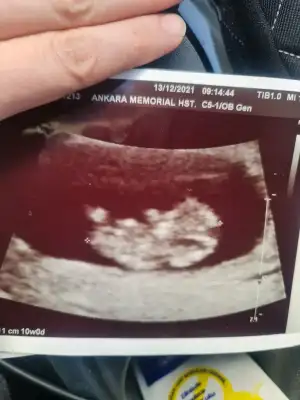

10+0 çıktı. Ikra meyra Ikra meyra ve diğer arkadaşlar umarım bellidir😁

Erkek ve kız için 11 + 12+ yada 13 hafta usg görüntüsü olmalı açıklamalar asagıda yazıyor 😊 rabbim herkesin gönlüne göre nasip etsin inşallah .. ecmain

Eki Görüntüle 473829 bu bir erkek bebek genital nub cikintisi gayet yukarda

Eki Görüntüle 473831 simdi burada cikintilara bakin eger bel popo cizgisine paralel ise kiz

yok 30 derecelik bir aciyla yukari bakiyorsa erkek

yabancilarin hepsi biliyor bunu biz neden eksik kalalim gayet bilimsel simdi ellerinde11 12 13 ultrason fotografi olanlar alsin hemen baksin yada koyalim buraya yorumlayalim